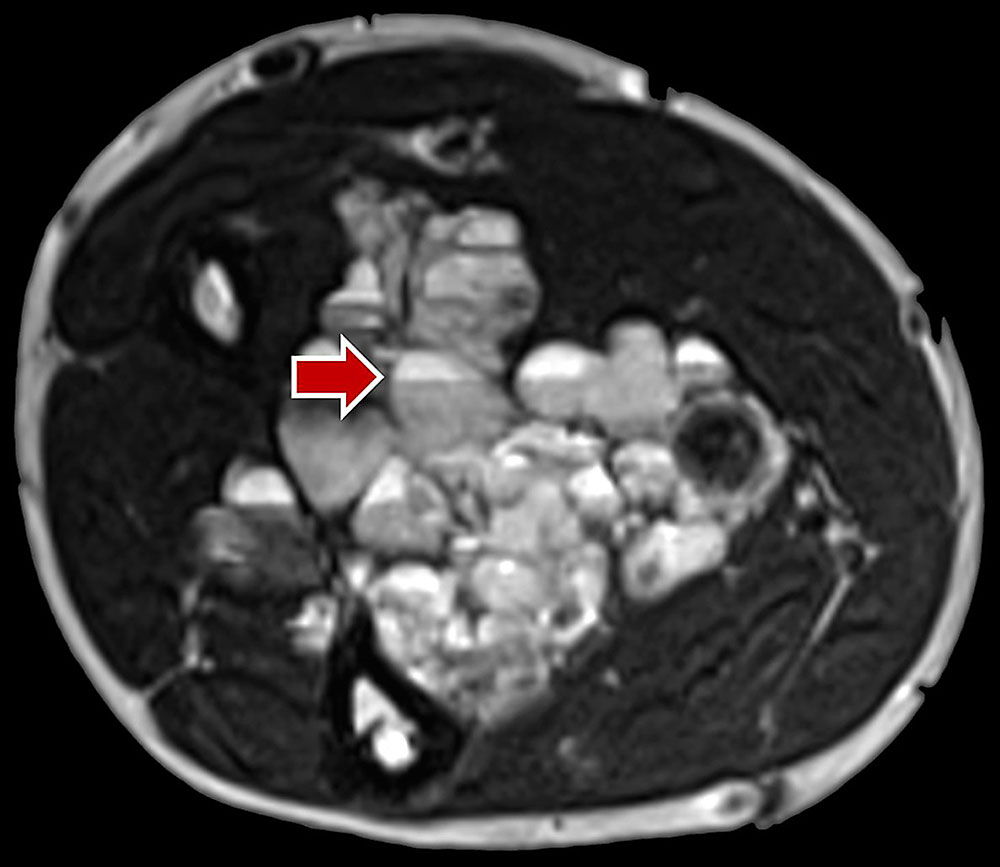

Venous malformation: In T2-weighted sequences, a strongly hyperintense signal predominates, which is highly visible on fat-suppressed T2-weighted sequences (STIR). Here they appear as septated, lobulated sponge-like or tubular masses, but often without any real space-occupying effect. Usually, venous malformations are isointense to the surrounding musculature on non-enhanced T1-weighted sequences. Spherical structures within the lesion with low signal on all sequences correspond to thrombi or calcified phleboliths which are pathognomonic for venous malformations when intralesional. Fluid-fluid levels can also be observed due to sedimentation phenomena within the venous malformations, but these are less frequent than in lymphatic malformations. After application of contrast medium, venous malformations slowly enhance contrast medium homogeneously. The average time to full contrast agent enhancement is about 90 seconds, which is significantly longer than for arteriovenous malformations (< 5 seconds). In contrast to arteriovenous malformations, in venous malformations the arteries supplying the affected extremity are not dilated. Flow voids are missing in venous malformations. Therapy-relevant venous connections (communicating veins) between the venous malformation and the deep venous system are occasionally identifiable on MRI. Abnormalities such as aplasia or hypoplasia of the deep and superficial venous system are also detectable.